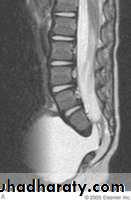

Plain roentgenograms demonstrate a defect in the vertebra, and CT scanning or MRI outlines the extent of the meningocele.

Myelomeningocele

It is a spinal meningocele that contains nerve roots & some times spinal cord tissue & is always associated with mid line defects of the vertebral neural arches, muscle, subcutaneous connective tissues & skin.This condition produces dysfunction of many organs and structures, including the skeleton, skin, GIT & GUT, in addition to the peripheral nervous system and the CNS.